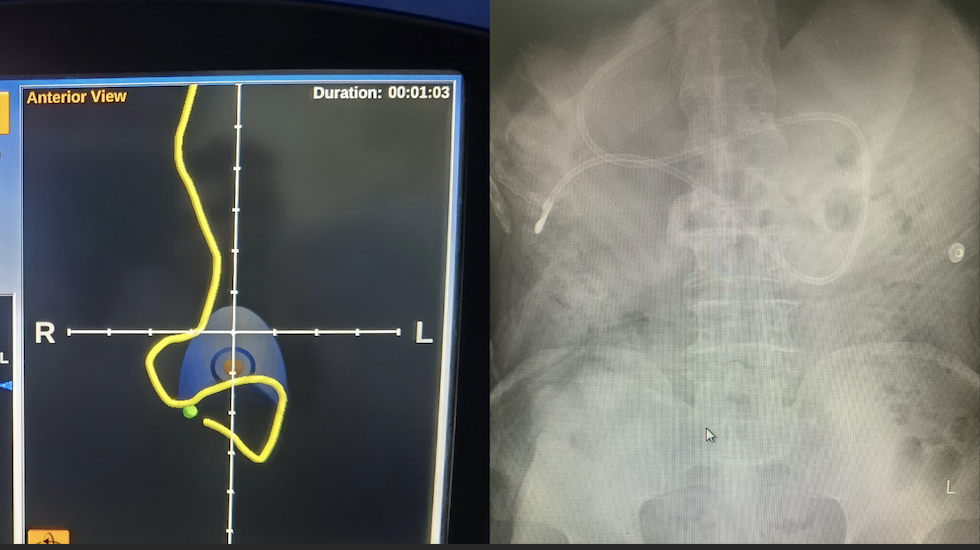

10月8日,营养科主治医师冯果接到内科ICU会诊申请。有一名87岁高龄老人俯卧位通气返流明显,需要置入鼻空肠管。然而,这名患者是一名罕见的内脏反位的“镜面人”,他的主动脉、心脏、脾脏、胃泡等本应位于左侧的器官均位于右侧,非内窥镜下置入鼻空肠管的难度极大。

冯果医生仔细了解了患者的病情,浏览了CT图像,并向影像科郑薇医生请教阅片,反复确定胃、幽门、十二指肠的走形,当日上午便为患者在磁导航引导下置入鼻空肠管。由于准备工作充分,只花了不到10分钟便顺利将导管置入空肠段,置入深度110厘米。

鼻空肠管置管是实现幽门后喂养的一种途径,在临床尤其是在重症患者的营养支持中发挥重要作用。磁导航下的鼻空肠管置管无辐射,不受视线遮挡的影响,做到更安全,更迅速,更准确。湘雅三医院营养科在省内率先开展“磁导航下鼻空肠营养管置管术”,2022年在中南大学及湘雅三医院获得该项目的临床新技术项目立项。2023年,“徒手及联合磁导航经鼻空肠管置管术临床应用”获批“国家卫生健康技术重点推广项目”,目前已推广至省外和省内多家医院。